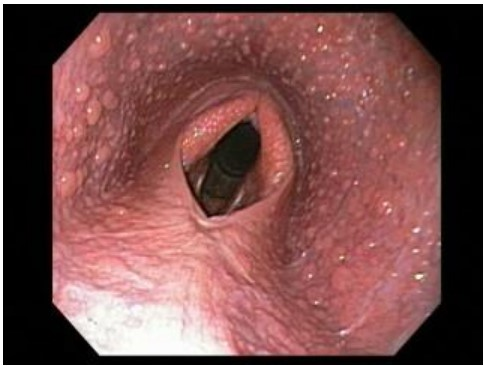

O exame endoscópico auxilia no diagnóstico e classificação das afecções das vias aéreas dos equinos. Considerando esse contexto, observe a imagem abaixo e assinale o enunciado CORRETO que indica a doença apresentada no exame endoscópico.

Enunciado 4583265-1

FONTE: https://vethospital.tamu.edu/large-animal/ … Data de acesso: 13/12/2023 (Adaptada).